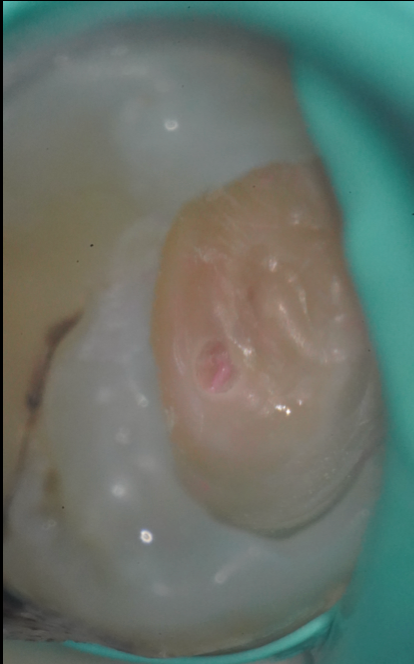

治療後

神経が見えてしまった

ときは、即座に

VPTを行います

虫歯が深く進行していると、治療中に歯髄(神経)に達することがあります。

その場合、従来では「神経を全部取る(抜髄)」という処置が一般的でしたが、歯の寿命を延ばすためには神経を残すことが理想です。

そこで当院では、可能な限り「VPT(Vital Pulp Therapy:生活歯髄療法)」を選択します。

これは、露出した歯髄を保護し、神経を残すための高度な処置です。